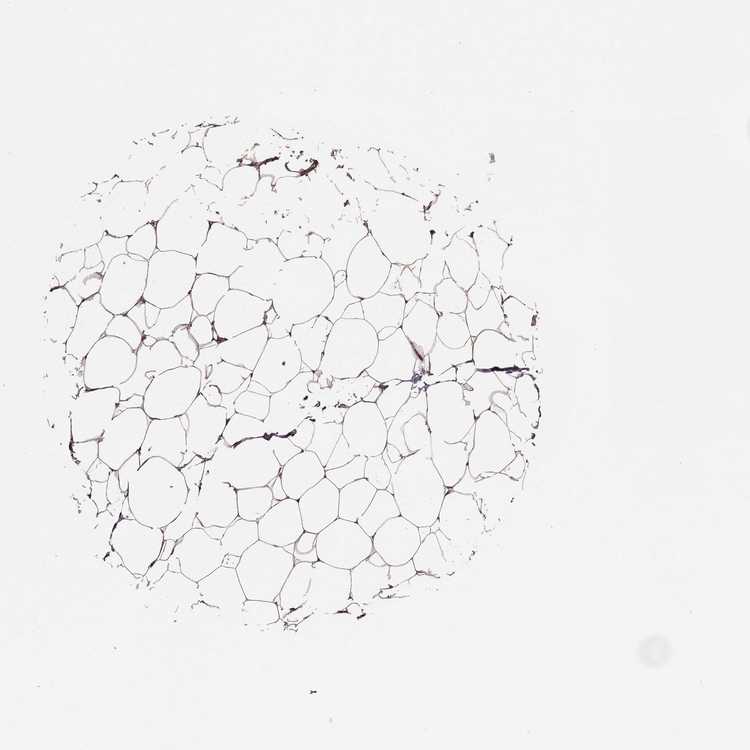

BREAST - Antibody stainingi

Antibody staining in the annotated cell types in the current human tissue is reported as not detected, low, medium, or high, based on conventional immunohistochemistry profiling in selected tissues. This score is based on the combination of the staining intensity and fraction of stained cells.

Each image is clickable and will lead to virtual microscopy that enables deeper exploration of all samples and also displays staining intensity scores, fraction scores and subcellular localization as well as patient and tissue information for each sample.

Antibody HPA017959Antibody HPA030549

Adipocytes MediumMedium

Glandular cells MediumHigh

Myoepithelial cells MediumMedium